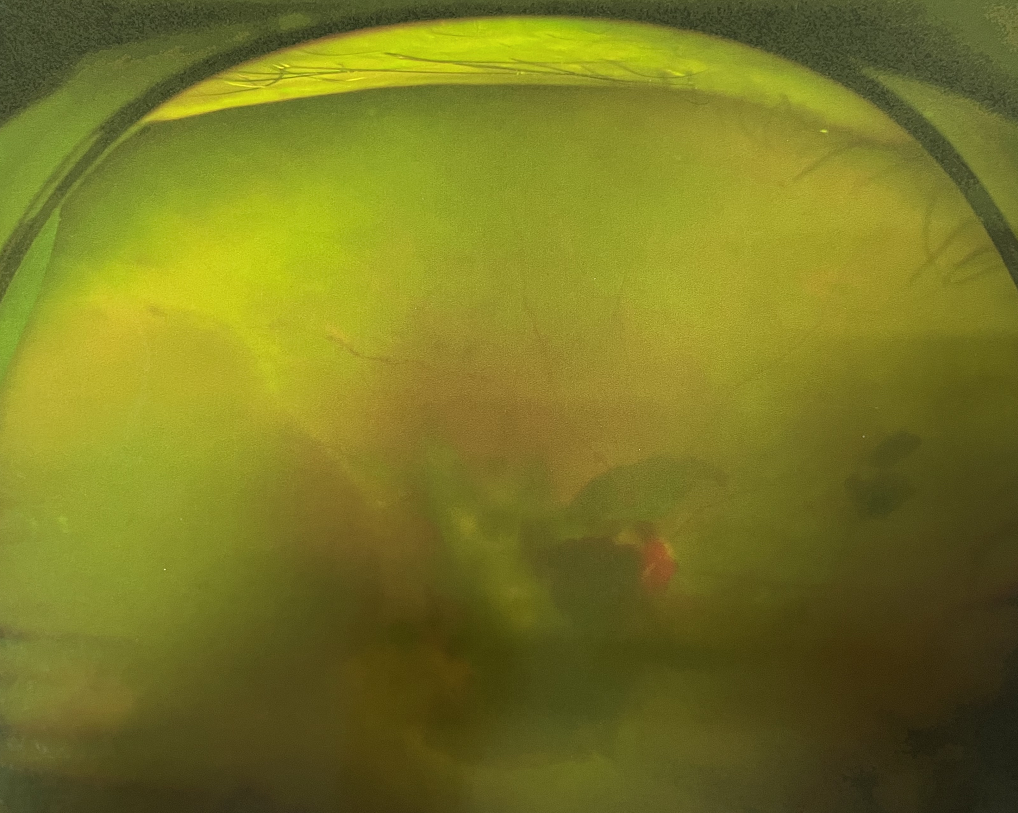

【文章導(dǎo)讀】糖尿病視網(wǎng)膜病變是糖尿病在眼部的主要并發(fā)癥,是我國(guó)四大致盲眼病之一,主要以視網(wǎng)膜血管改變?yōu)椴±硖卣?。眼底多表現(xiàn)為視網(wǎng)膜出血、滲出、新生血管及增殖膜形成,嚴(yán)重威脅患者

糖尿病視網(wǎng)膜病變是糖尿病在眼部的主要并發(fā)癥,是我國(guó)四大致盲眼病之一,主要以視網(wǎng)膜血管改變?yōu)椴±硖卣?。眼底多表現(xiàn)為視網(wǎng)膜出血、滲出、新生血管及增殖膜形成,嚴(yán)重威脅患者的視覺(jué)健康。

糖尿病視網(wǎng)膜病變

糖尿病視網(wǎng)膜病變可分為六期:

?、衿冢河形⒀芰龌虿⒂行〕鲅c(diǎn)。

?、蚱冢河悬S白色“硬性滲出”或并有出血斑。

?、笃冢河邪咨?ldquo;軟性滲出”或并有出血斑。

?、羝冢貉鄣子行律芑虿⒂胁Aw積血。

?、跗冢貉鄣子行律芑虿⒂欣w維膜增生。

Ⅵ期:眼底有新生血管或并有纖維膜增生,并發(fā)視網(wǎng)膜脫離。